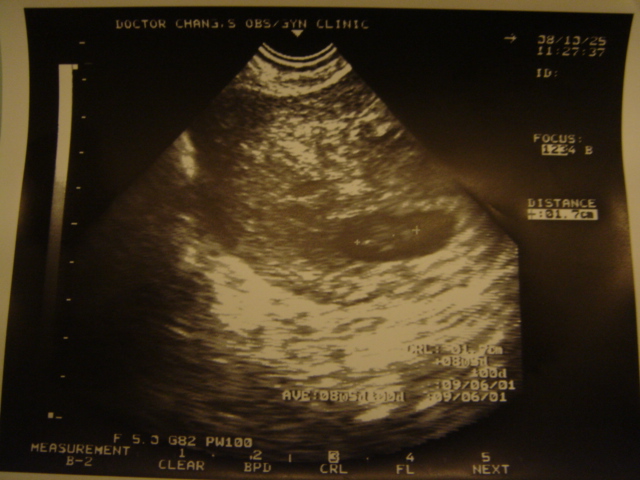

每次要去我們家小bb時 總是特別緊張

擔心他小小心跳不見了 或是 沒有繼續長大